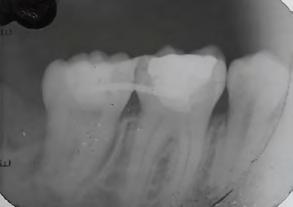

Paciente masculino de 29 años de edad, sin antecedentes médicos de interés acude al servicio de Cirugía Maxilofacial, el cual acude a la con sulta por odontalgía asociado al pri mer molar inferior izquierdo (Figura 1). Realizamos estudios radiográficos de dicho órgano (Figura 2), siendo valorado por especialista en prótesis y endodoncia quienes refieren no ser candidato para rehabilitación y tra tamiento de conductos con un pro nóstico poco favorable. Motivo por el cual se ofrece la opción de realizar TD del tercer molar inferior izquierdo al lecho quirúrgico del primer molar

Figura 2. Radiografía dentoalveolar inicial. Trasplante dental de terceros molares